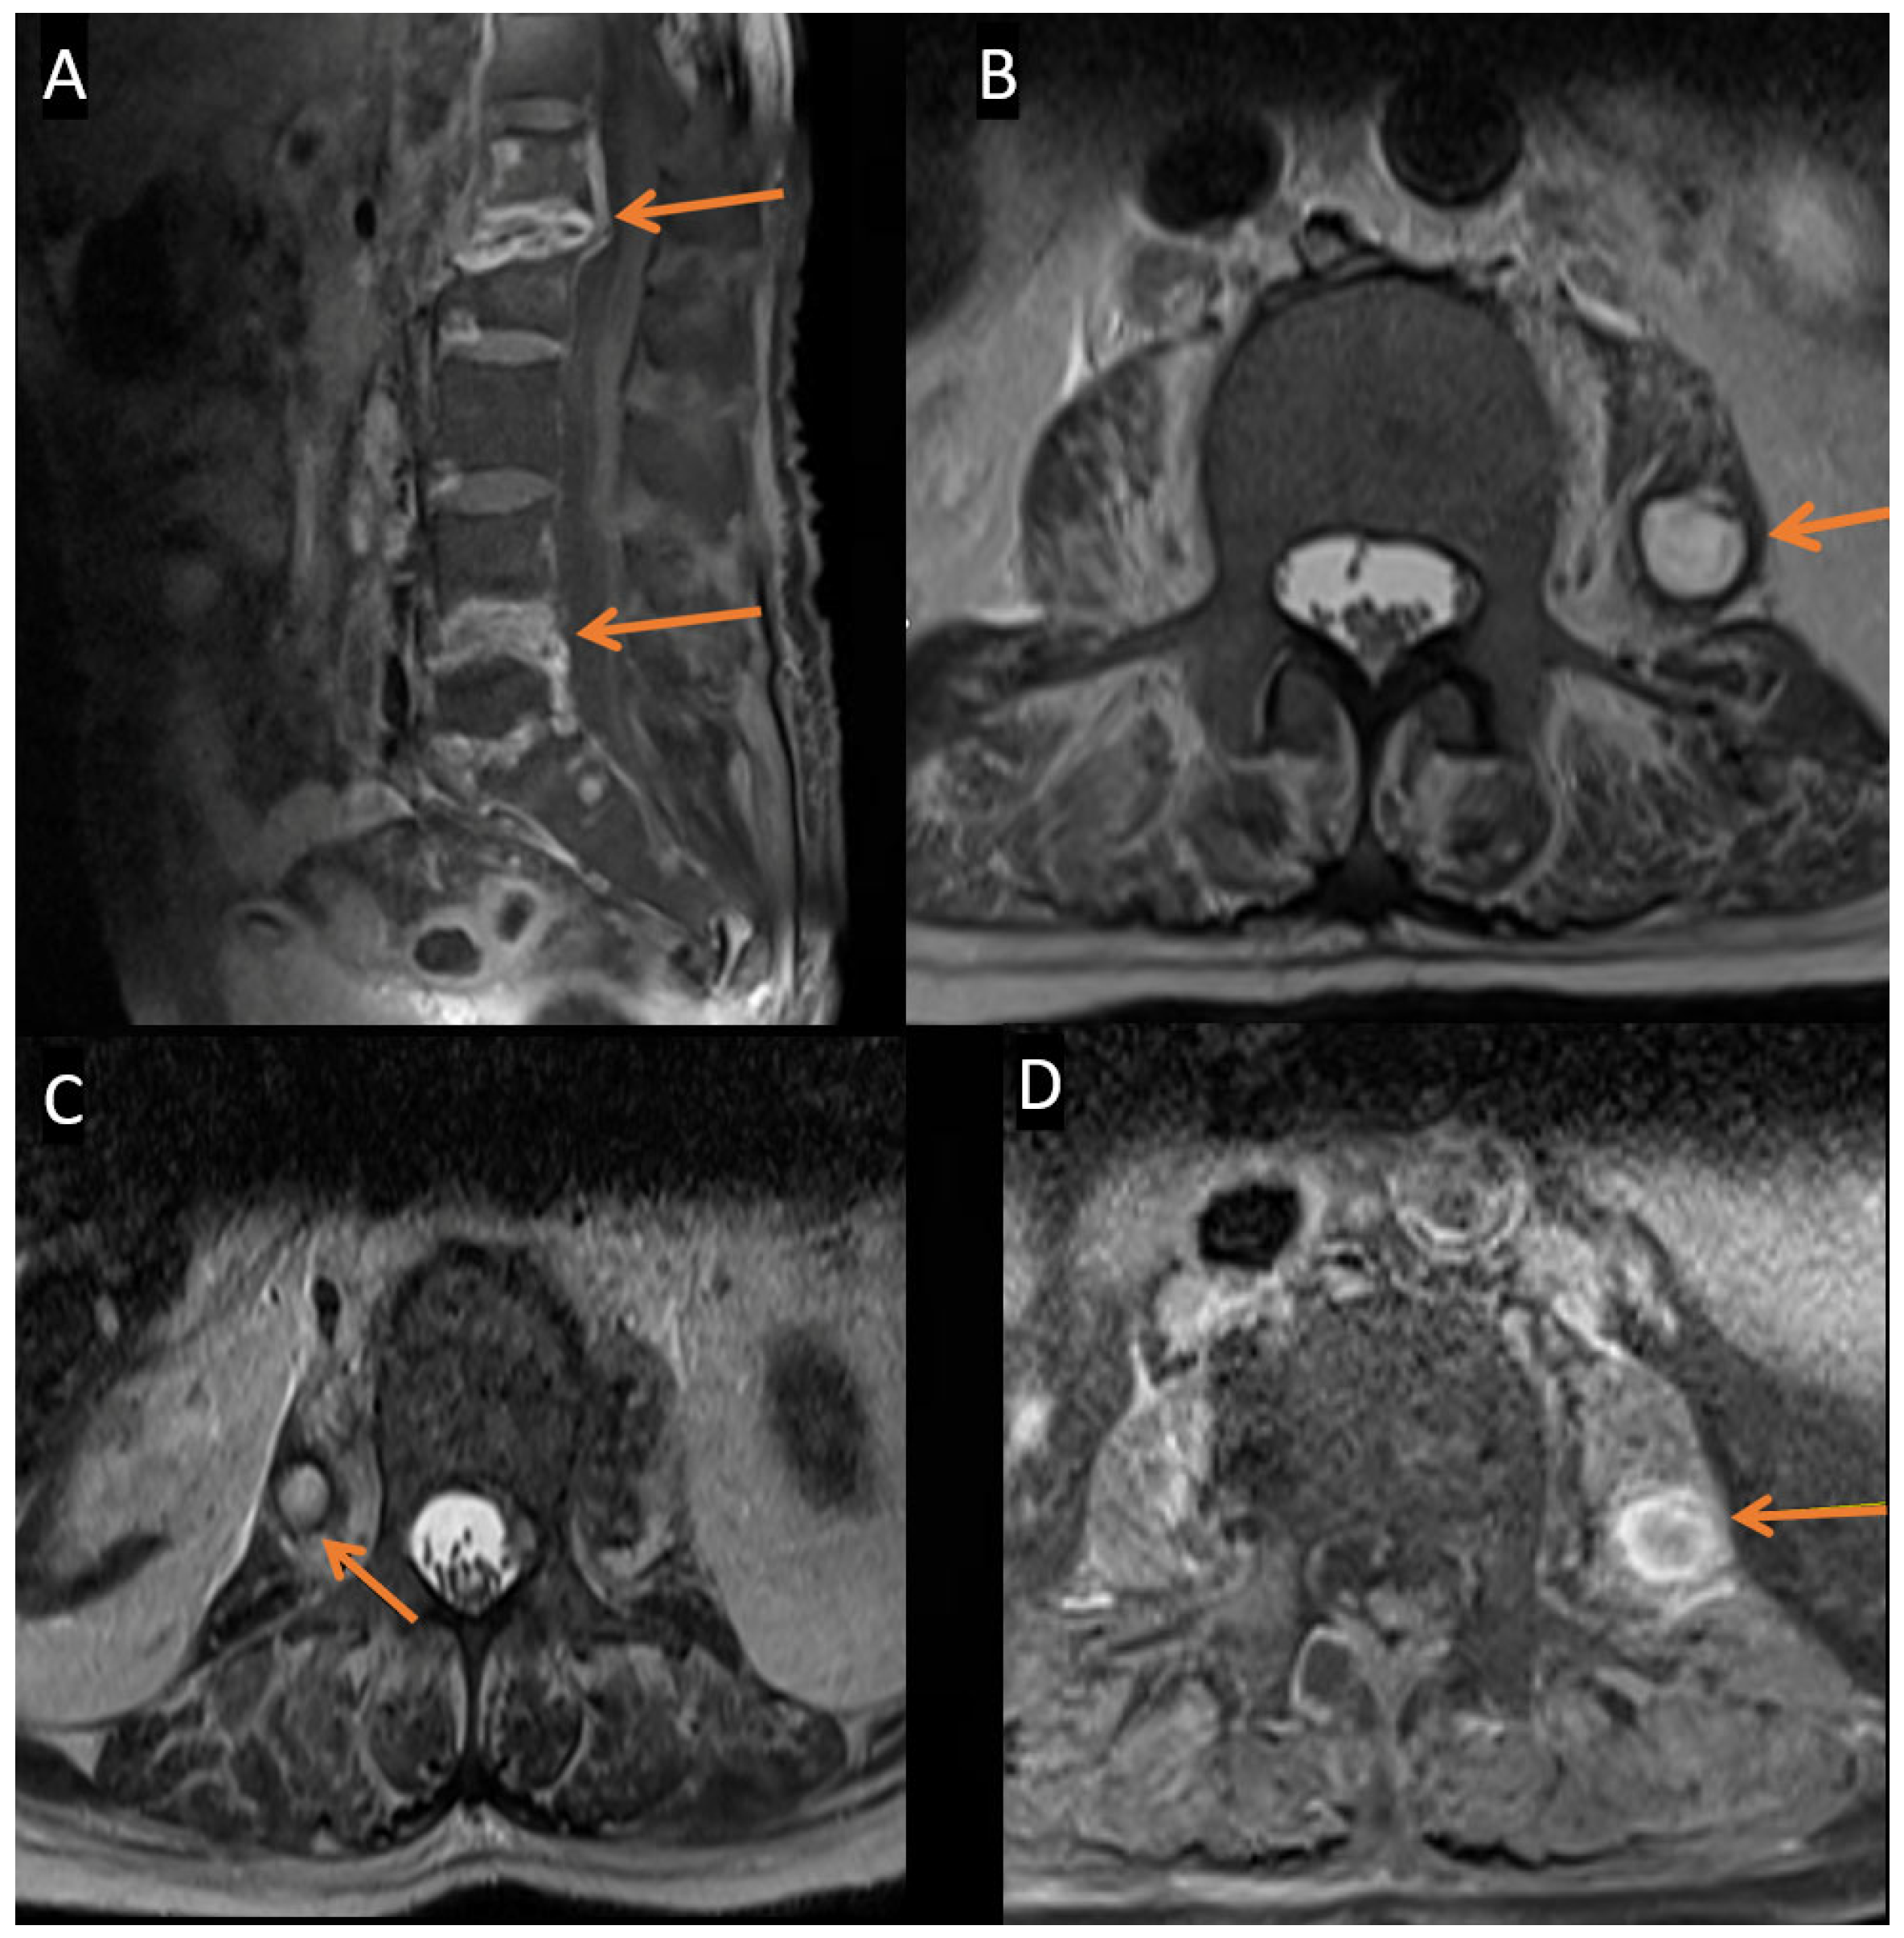

2. Case Description